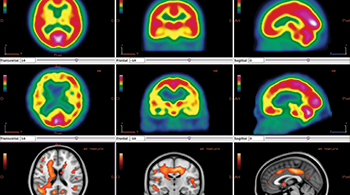

All Dosimetry Neurology Oncology Patient QA Segmentation Simulation & Treatment Planning Oncology PLANET® Onco Dosimetry PLANET® Dose Neurology PLANET® Neuro Segmentation IMAgo Segmentation MorphoBOX Simulation & Treatment Planning SIMAgo Simulation & Treatment Planning ISOgray® Simulation & Treatment Planning ISOgray®-Proton Patient QA ThinkQA Suite Patient QA MU2net Patient QA EPIbeam Patient QA EPIgray®